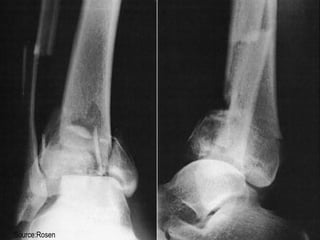

 The ankle is a ring

◦ Tibial plafond

◦ Medial malleolus

◦ Deltoid ligaments

◦ calcaneous

◦ Lateral collateral ligaments

◦ Lateral malleolus

◦ Syndesmosis

 Fracture of single part usually

stable

 Fracture > 1 part = unstable

Source: Rosen